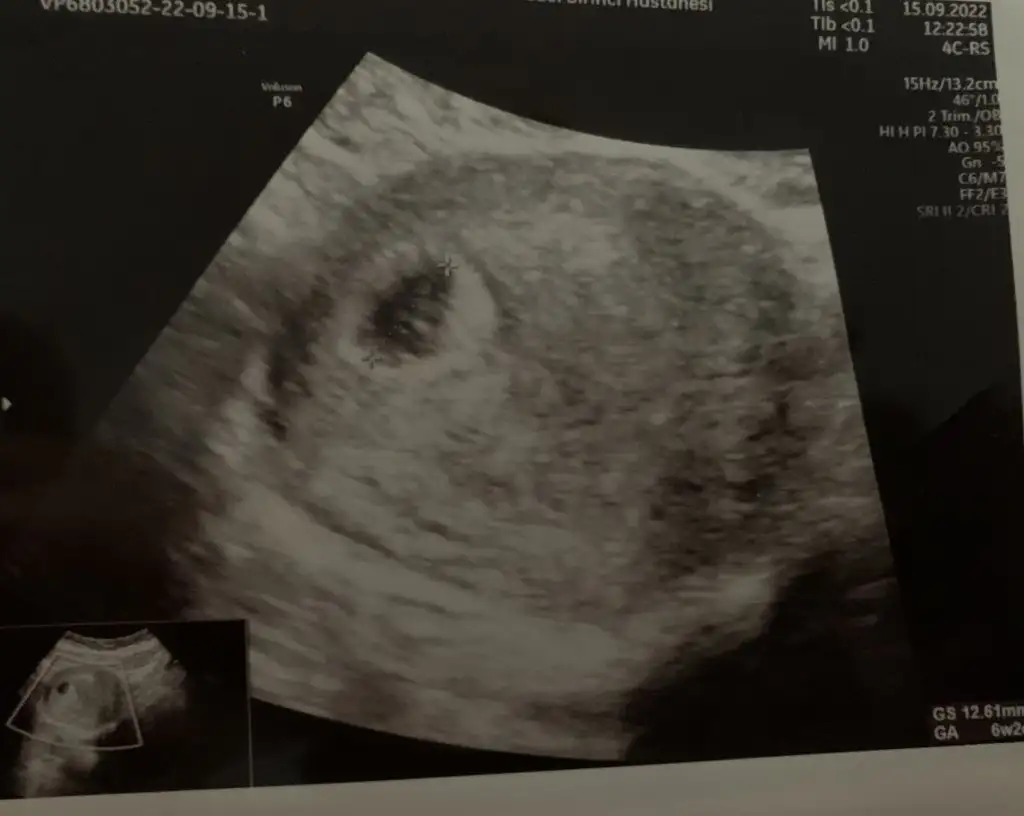

Maşallah daha nice ultrasonlarını göreceğiz inşallahBugün miniğimi çok ufak da olsa görebildik çok şükür ki. Hatta çok az kalp atışını da duyduk. Devlet hastanesinde muayene olduğum doktorlar o kadar olumsuz konuşuyordu ki dış gebelik mi boş gebelik mi diye günlerdir kendimi yiyordum. Herşey yolundaymış neyse ki. Doktorum bundan sonra hcg testi yapmana gerek yok, ultrasonla takibe devam ediyoruz dedi. Haftaya cuma tekrar kontrolümüz var

Gözün aydın canim kac haftaliksiniz suanBugün miniğimi çok ufak da olsa görebildik çok şükür ki. Hatta çok az kalp atışını da duyduk. Devlet hastanesinde muayene olduğum doktorlar o kadar olumsuz konuşuyordu ki dış gebelik mi boş gebelik mi diye günlerdir kendimi yiyordum. Herşey yolundaymış neyse ki. Doktorum bundan sonra hcg testi yapmana gerek yok, ultrasonla takibe devam ediyoruz dedi. Haftaya cuma tekrar kontrolümüz var